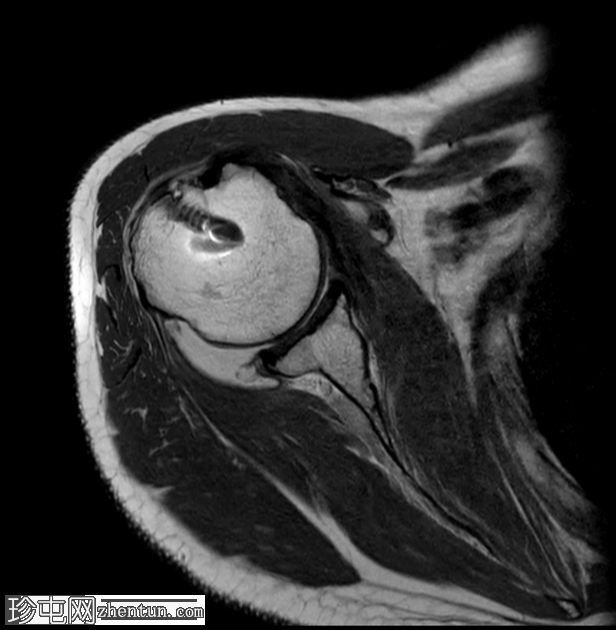

矢状位

PD加权像

冈下肌腱在其骨性附着点处也显示出异常高PD信号和纤维断裂,符合高等级部分撕裂的特征;然而,该肌腱并未完全从肱骨大结节脱离。

肩胛下肌腱也显示出​​肌腱病,伴有部分撕裂。

肱二头肌长头肌腱位于肱二头肌沟内,外观完整,但存在轻度腱鞘炎。

肩关节内存在轻至中度关节积液。